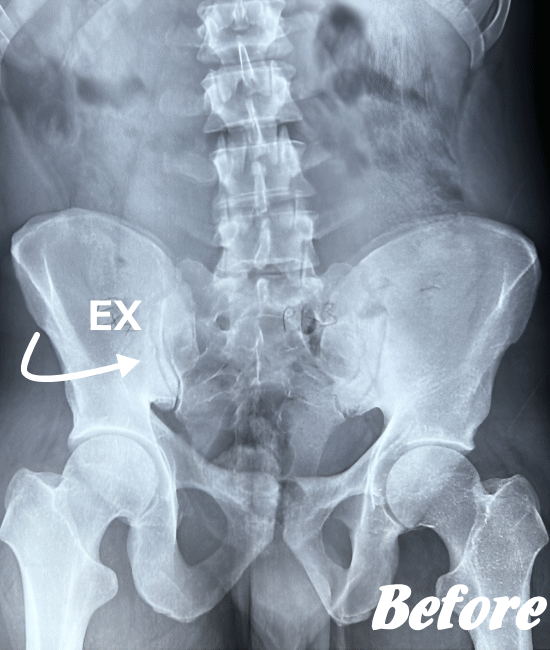

仙腸関節自体はごくわずかな動きしかありませんので、レントゲンやCT、MRIなどでは画像診断で判別することが難しいと言われています。

したがって、画像検査が難しいため、仙腸関節障害の診断は、症状経過と仙腸関節部の圧迫テストで診断されます。

HALOカイロプラクティック☆平和島整体院では、仙腸関節の動きやズレを回復させることを第一に考慮した施術を行っています。たとえ、足や肩の痛みやしびれが主訴であっても、仙腸関節を正しい状態に戻すことから施術を始めています。

仙腸関節、股関節、脊柱を特に集中して解剖学的に正しい位置へと戻す施術になります。HALOカイロプラクティック☆平和島整体院では、医療機関でも用いられているAKA療法も取り入れて施術しています。